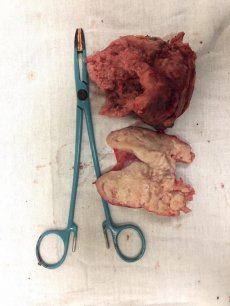

У першому випадку операція тривала годину і двадцять хвилин. Пацієнту проводили радикальну нефректомію (операція з видалення нирки, - прим.авт.) Під час операції медики також видалили пухлину вагою 2 кілограми.

Другому пацієнту видаляли пухлину позаочеревинного простору. Операція тривала годину і 40 хвилин. Маса пухлини – 1,5 кілограма.